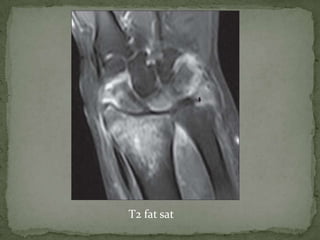

• lytic area of bone

destruction

• transphyseal spread of

infection across the

growth plate

T2 fat sat